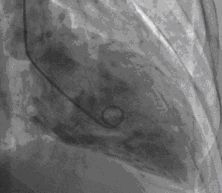

Cardiac catherization on hospital day 15 revealed normal coronary arteries (Figure 1) with anterobasal and posterobasal hyperkinesis, anterolateral and diaphragmatic hypokinesis, and distal ballooning on ventriculography. Ventriculography revealed global LV depression with EF of 45% (Figures 2, 3).

Fig2

Figure 2-Ventriculography revealed global LV depression with EF of 45%. This is the end diastolic frame of the left ventriculogram.